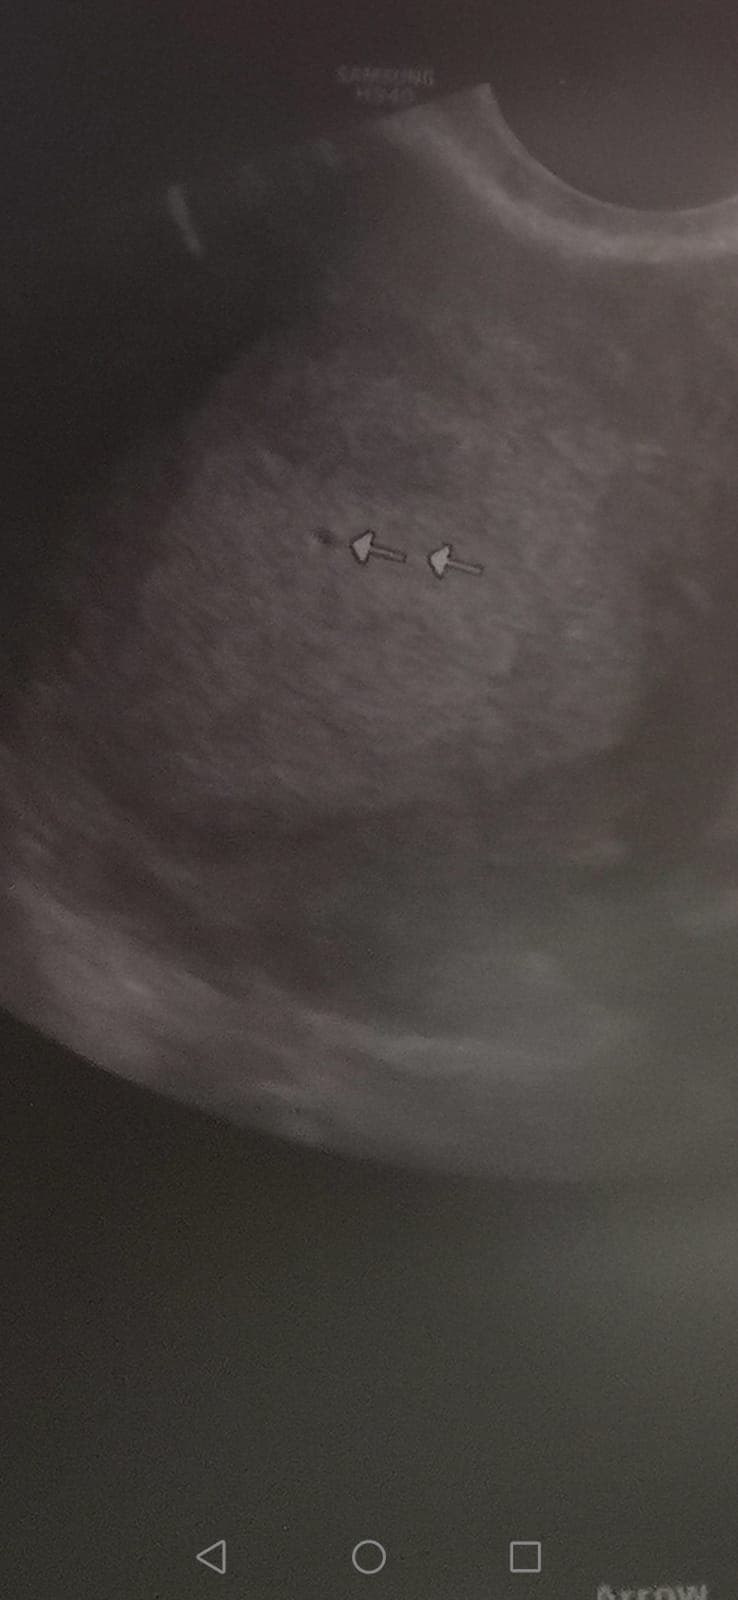

Dziewczyny, tak jeszcze patrzę na to swoje pierwsze usg (w 4 tc je miałam), gdzie lekarka znalazła 0.5mm pęcherzyk w macicy. Nie wiem czemu mam wciąż wątpliwości, ale mam troszeczkę zrytą psychikę po ostatniej ciąży pozamacicznej i jak mnie zaboli po jednej stronie, to znowu wpadam w panikę. Czy tak wygląda taki maluteńki pęcherzyk?

Może któraś też poszła wcześniej do ginekologa i miała podobny?